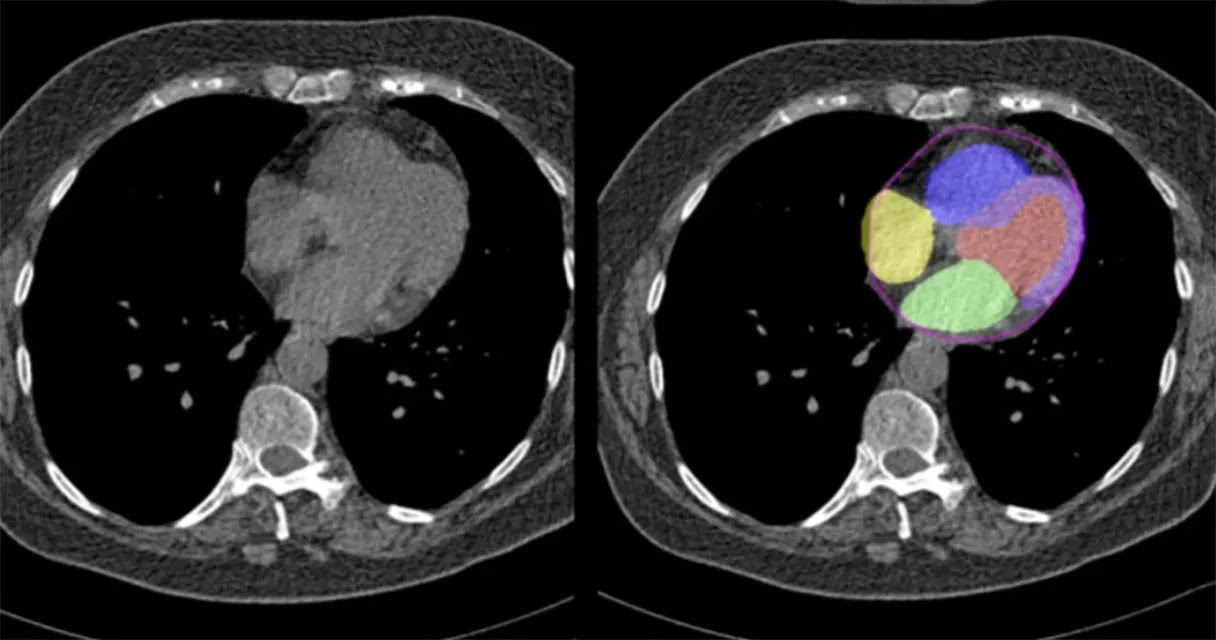

A CT scan creates detailed cross-sectional images of the body, including the heart, using X-ray technology and computer processing. Specialized forms like coronary calcium scoring or CT angiography are often used for heart-related assessments. These scans highlight abnormalities in coronary arteries, measure calcium deposits, and visualize blockages or structural issues.

These scans are non-invasive and highly effective in capturing detailed images, making them excellent diagnostic tools for assessing cardiovascular health. Their role lies in detecting structural changes in the arteries. This aids in offering insights into potential heart disease risks well before symptoms arise and enabling early treatment.